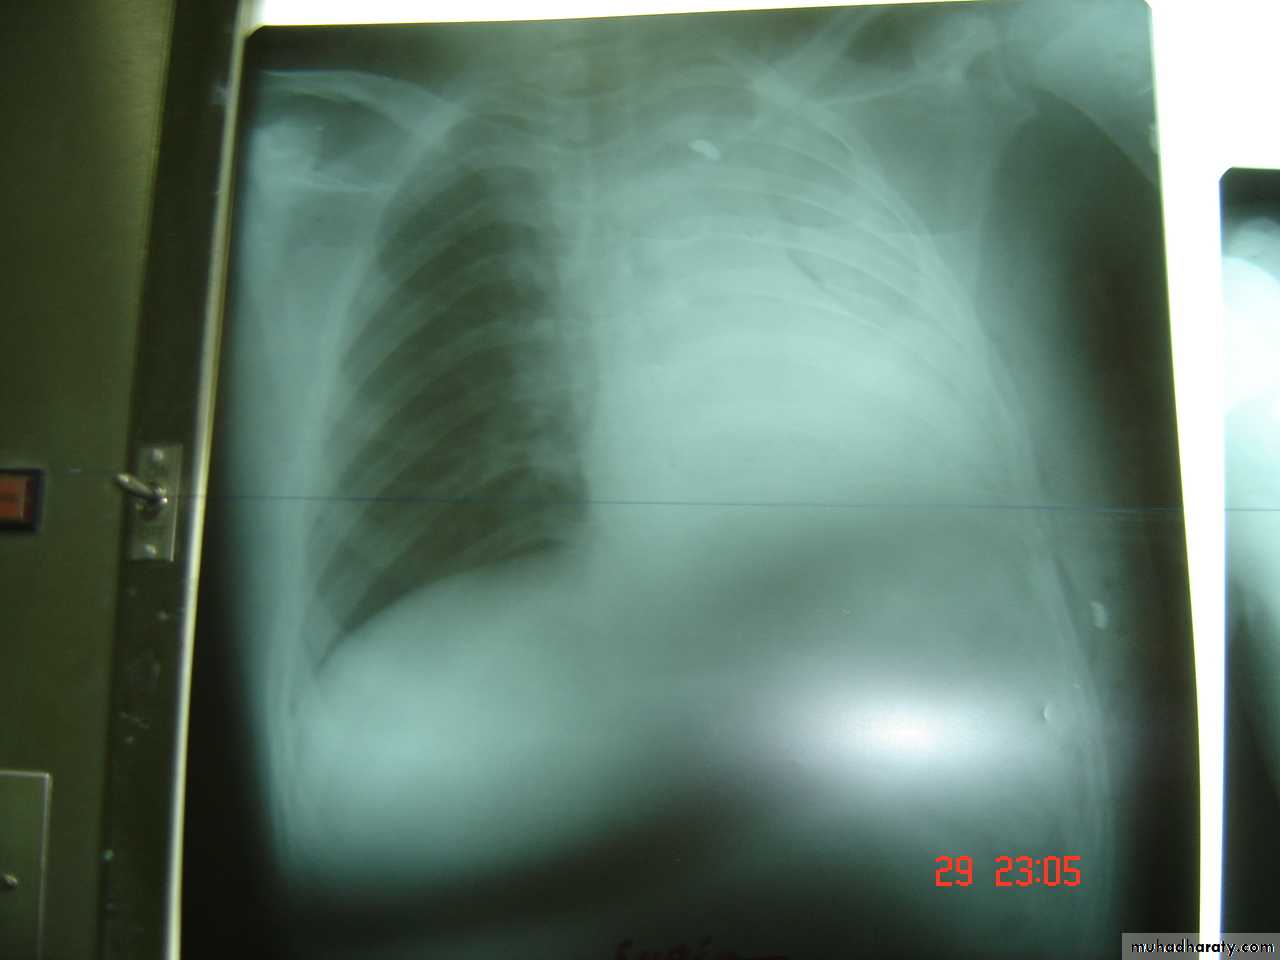

• 4-Pleural effusion

• Is the accumulation of fluid in the pleural space excessive transudation or exudation of the interstitial fluid from the pleural surface. It is signify pleural or systemic disease .

• Its effect depends on its size (mild , moderate or massive ) & the state of the underlying lung .It is classified as transudate when the protein content is less than 3g% or exudates when protein content is more than 3 gm % .Clinically patients will present with dyspnea & pleuritic chest pain

• Radio logically (concave meniscus sign)